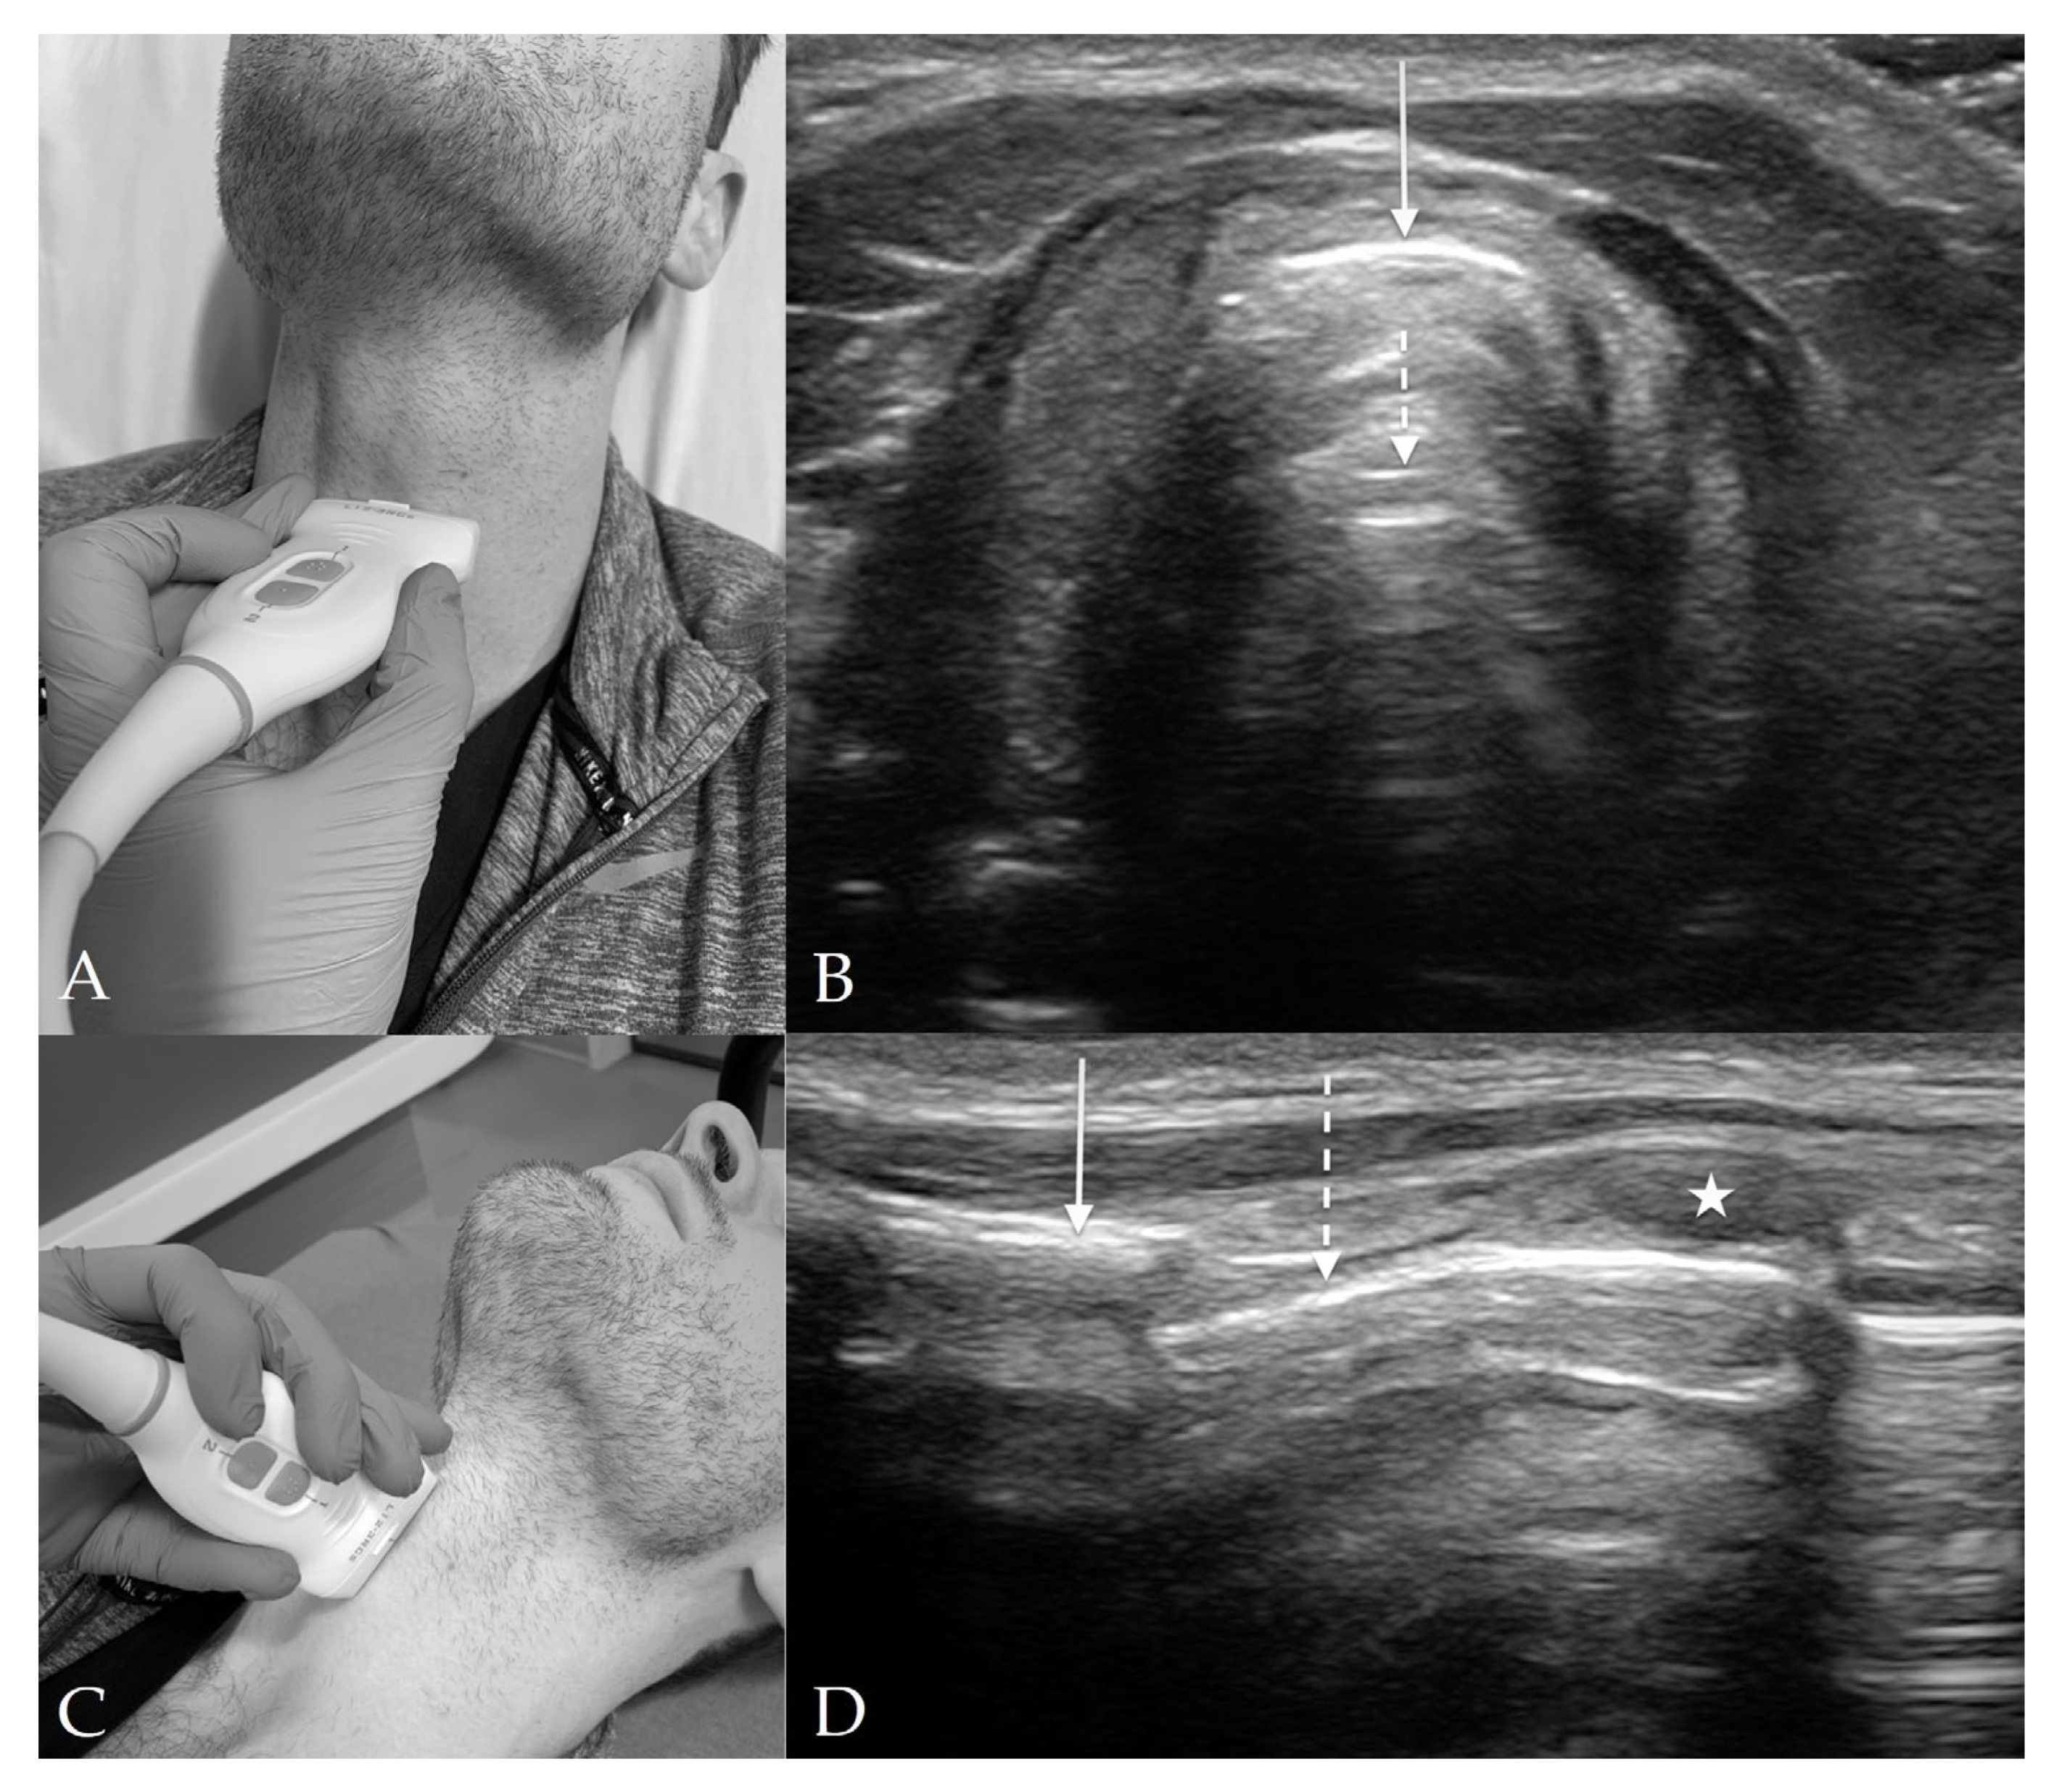

8. Preparation for Cricothyrotomy

- Kristensen, M.S.; Teoh, W.H.; Rudolph, S.S. Ultrasonographic identification of the cricothyroid membrane: Best evidence, techniques, and clinical impact. Br. J. Anaesth. 2016, 117 (Suppl. S1), i39–i48. [Google Scholar] [CrossRef] [PubMed]

- Rai, Y.; You-Ten, E.; Zasso, F.; de Castro, C.; Ye, X.Y.; Siddiqui, N. The role of ultrasound in front-of-neck access for cricothyroid membrane identification: A systematic review. J. Crit. Care 2020, 60, 161–168. [Google Scholar] [CrossRef]

- Hung, K.C.; Chen, I.W.; Lin, C.M.; Sun, C.K. Comparison between ultrasound-guided and digital palpation techniques for identification of the cricothyroid membrane: A meta-analysis. Br. J. Anaesth. 2021, 126, e9–e11. [Google Scholar] [CrossRef] [PubMed]

- Siddiqui, N.; Arzola, C.; Friedman, Z.; Guerina, L.; You-Ten, K.E. Ultrasound Improves Cricothyrotomy Success in Cadavers with Poorly Defined Neck Anatomy: A Randomized Control Trial. Anesthesiology 2015, 123, 1033–1041. [Google Scholar] [CrossRef] [PubMed]

- Kristensen, M.S. Ultrasonography in the management of the airway. Acta Anaesthesiol. Scand. 2011, 55, 1155–1173. [Google Scholar] [CrossRef]

- Kristensen, M.S.; Teoh, W.H.; Rudolph, S.S.; Hesselfeldt, R.; Børglum, J.; Tvede, M.F. A randomised cross-over comparison of the transverse and longitudinal techniques for ultrasound-guided identification of the cricothyroid membrane in morbidly obese subjects. Anaesthesia 2016, 71, 675–683. [Google Scholar] [CrossRef]